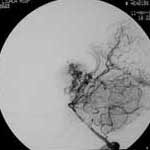

三、闭塞性脑血管病

----闭塞性脑血管病,如急性脑梗塞引起的偏瘫、颈动脉或椎基底动脉狭窄所致短暂性脑缺血发作(TIA)及可逆性神经功能障碍(RIND),视网膜中央动脉或中央静脉闭塞引起的视力减退,静脉窦血栓性形成引起的颅内压增高等,均可通过血管内的介入治疗得以改善,介入治疗的方法分溶栓、血管成形术或支架置入,根据病变选择不同的治疗方法。

2.急性梗塞动脉内接触性溶栓治疗的适应症:

(1)发病6小时内;

(2)CT或MEI检查没有梗塞及出血表现;

(3)对大脑中动脉卒中者,133XESPECT检查显示CBF残存超过每分钟15ml/100g;

(4)血管造影证实颅内血栓及部位;

(5)基底动脉溶栓可延至发病后48小时。